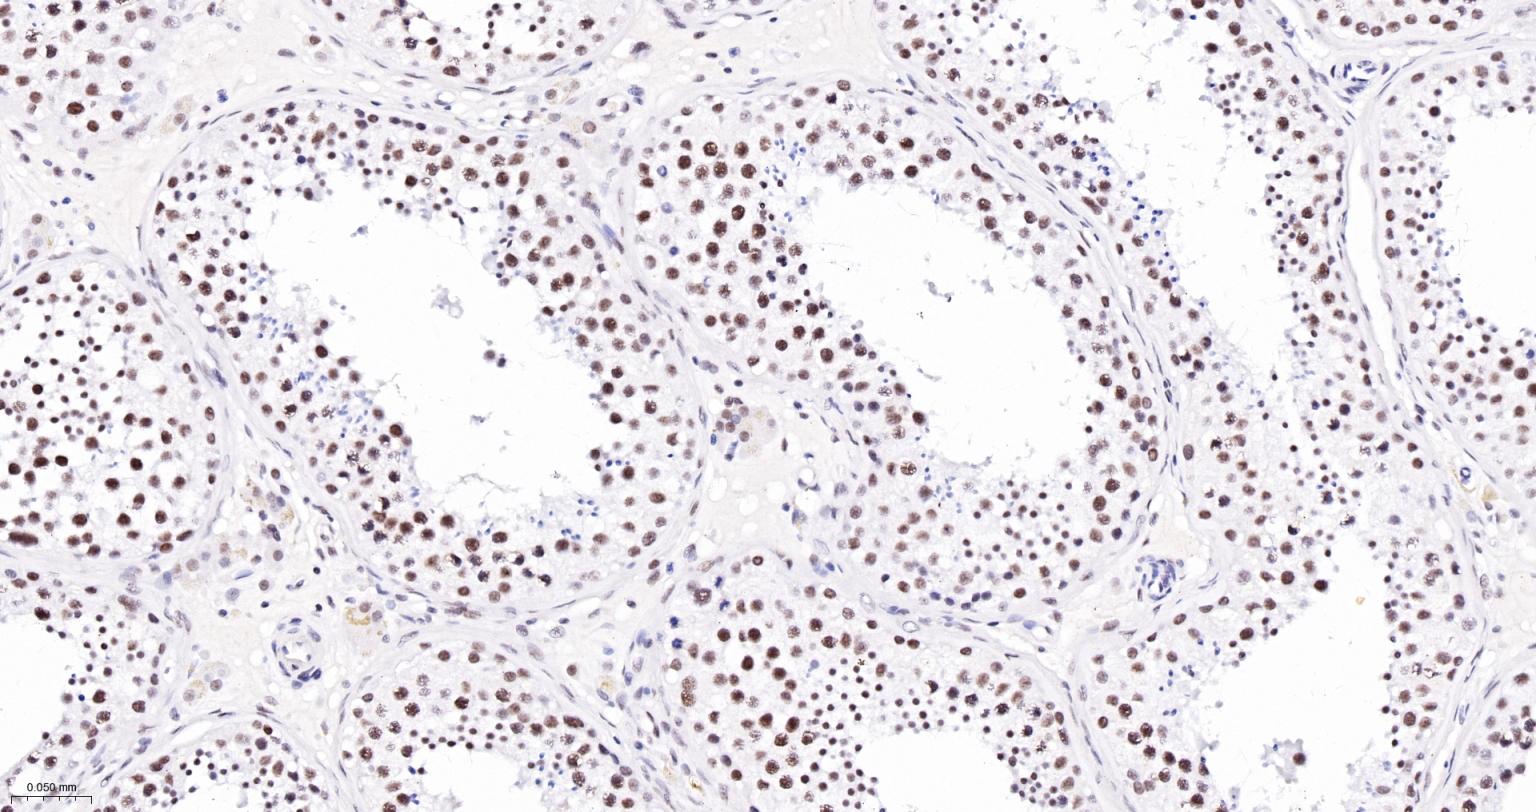

Paraformaldehyde-fixed, paraffin embedded Mouse Lung; Antigen retrieval by boiling in sodium citrate buffer (pH6.0) for 15 min; The section was incubated with USP39 Monoclonal Antibody, Unconjugated (bsm-63016R) at 1:200 overnight at 4°C, followed by conjugation to the bs-0295G-HRP and DAB (C-0010) staining.